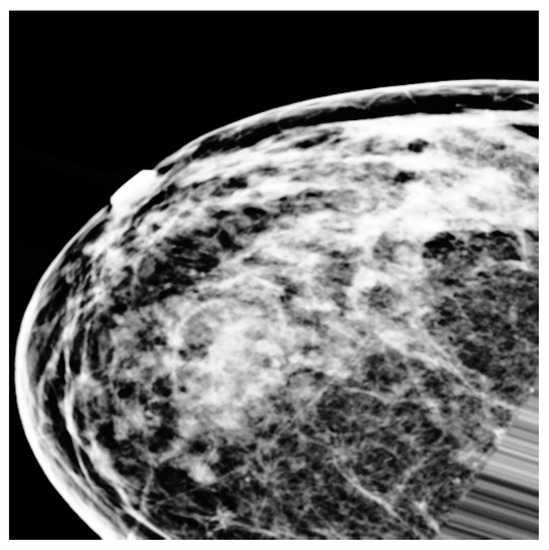

3.3. Preprocessing